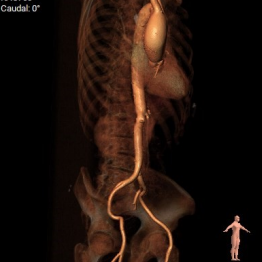

CT评估

1.瓣环及左室流出道。

2.主动脉瓣根部(左右瓣叶长度均超过冠脉高度)。

3.主动脉弓分析及瓣叶长度(最短弓距小于70mm)。

4.外周血管入路